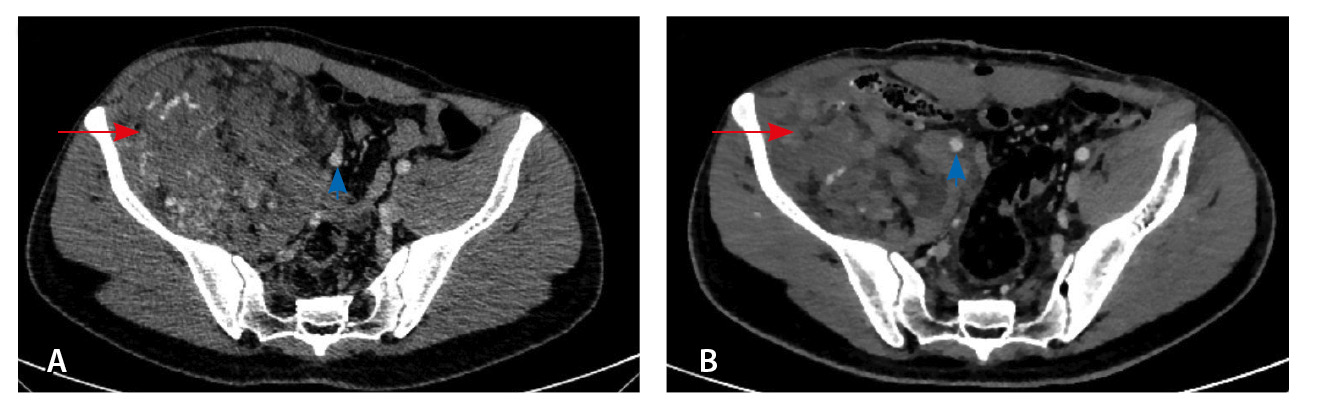

Результаты дооперационной мультиспиральной компьютерной томографии органов брюшной полости и забрюшинного пространства (рис. 1, 2): «В забрюшинном пространстве справа визуализируется образование, исходящее из подвздошно-поясничной мышцы, с выходом вдоль сосудистого пучка на верхнюю треть бедра. Образование с четкими и ровными контурами, размерами 145 × 125 × 125 мм. Структура образования гетерогенная, плотность в нативную фазу исследования от –40 до 50 HU, содержит единичные кальцинаты, жировую ткань и мягкотканный компонент. На фоне контрастирования в артериальную и венозную фазы в структуре выявляются извитой формы участки гиперконтрастирования (сосудистая сеть). Максимальное накопление контрастного препарата происходит преимущественно к отсроченной фазе исследования. Усредненные плотностные характеристики составляют 25, 36, 53 и 59 HU в нативную, артериальную, венозную и отсроченную фазы соответственно. Опухоль оттесняет тазовую брюшину, правую подвздошно-поясничную мышцу, илеоцекальный угол кпереди. Образование тесно прилежит сзади к крылу правой подвздошной кости и лобковой кости, спереди – к прямой и внутренней косым мышцам живота, верхним контуром – к поясничной мышце. Медиально в средней трети по контуру образования проходят правые наружные и внутренние подвздошные сосуды, со сдавлением наружной подвздошной вены. Данных за распространение на прилежащие внутренние органы и клетчатку не получено. Кости без деструктивных изменений».

Рис. 1. Мультиспиральная компьютерная томография органов брюшной полости и забрюшинного пространства с болюсным внутривенным контрастированием: А – нативная фаза, Б – артериальная фаза, В – венозная фаза, Г – отсроченная фаза. Крупное гетерогенной структуры образование забрюшинного пространства справа, с фокусами гиперваскуляризации в структуре. Тесно прилежит к крылу подвздошной кости и подвздошным сосудам, оттесняя последние медиально

Рис. 3. Мультиспиральная компьютерная томография органов брюшной полости и забрюшинного пространства с болюсным внутривенным контрастированием, венозная фаза. А – исследование до операции, Б – исследование после операции: резидуальный фрагмент образования (красная стрелка) тесно прилежит к подвздошной кости и подвздошным сосудам (головка синей стрелки)